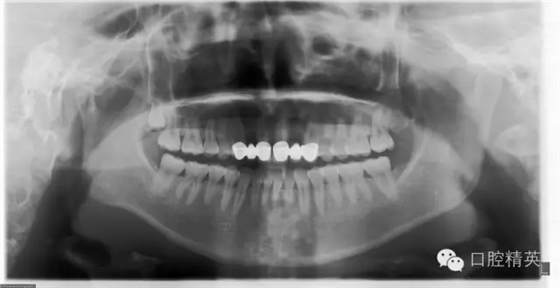

檢查:12及22缺失,13、12、11固定修復(fù)體,21、22、23固定修復(fù)體,11、13、21、23修復(fù)體邊緣不密合,修復(fù)體顏色偏黃,叩痛(—),不松動(dòng),13、23牙齦退縮,11、13、21、23牙齦發(fā)暗,覆牙合覆蓋關(guān)系大致正常。口腔衛(wèi)生狀況尚可。X線片示13、11、21及23牙根長(zhǎng)度可,根尖區(qū)無(wú)明顯病變,牙槽骨無(wú)明顯吸收。12、22缺失。